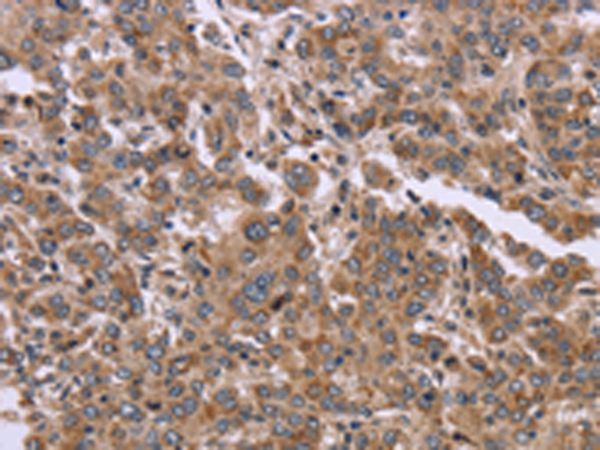

分类: 科研抗体货号: P08321别名:应用: IHC反应种属: Human, Mouse, Rat